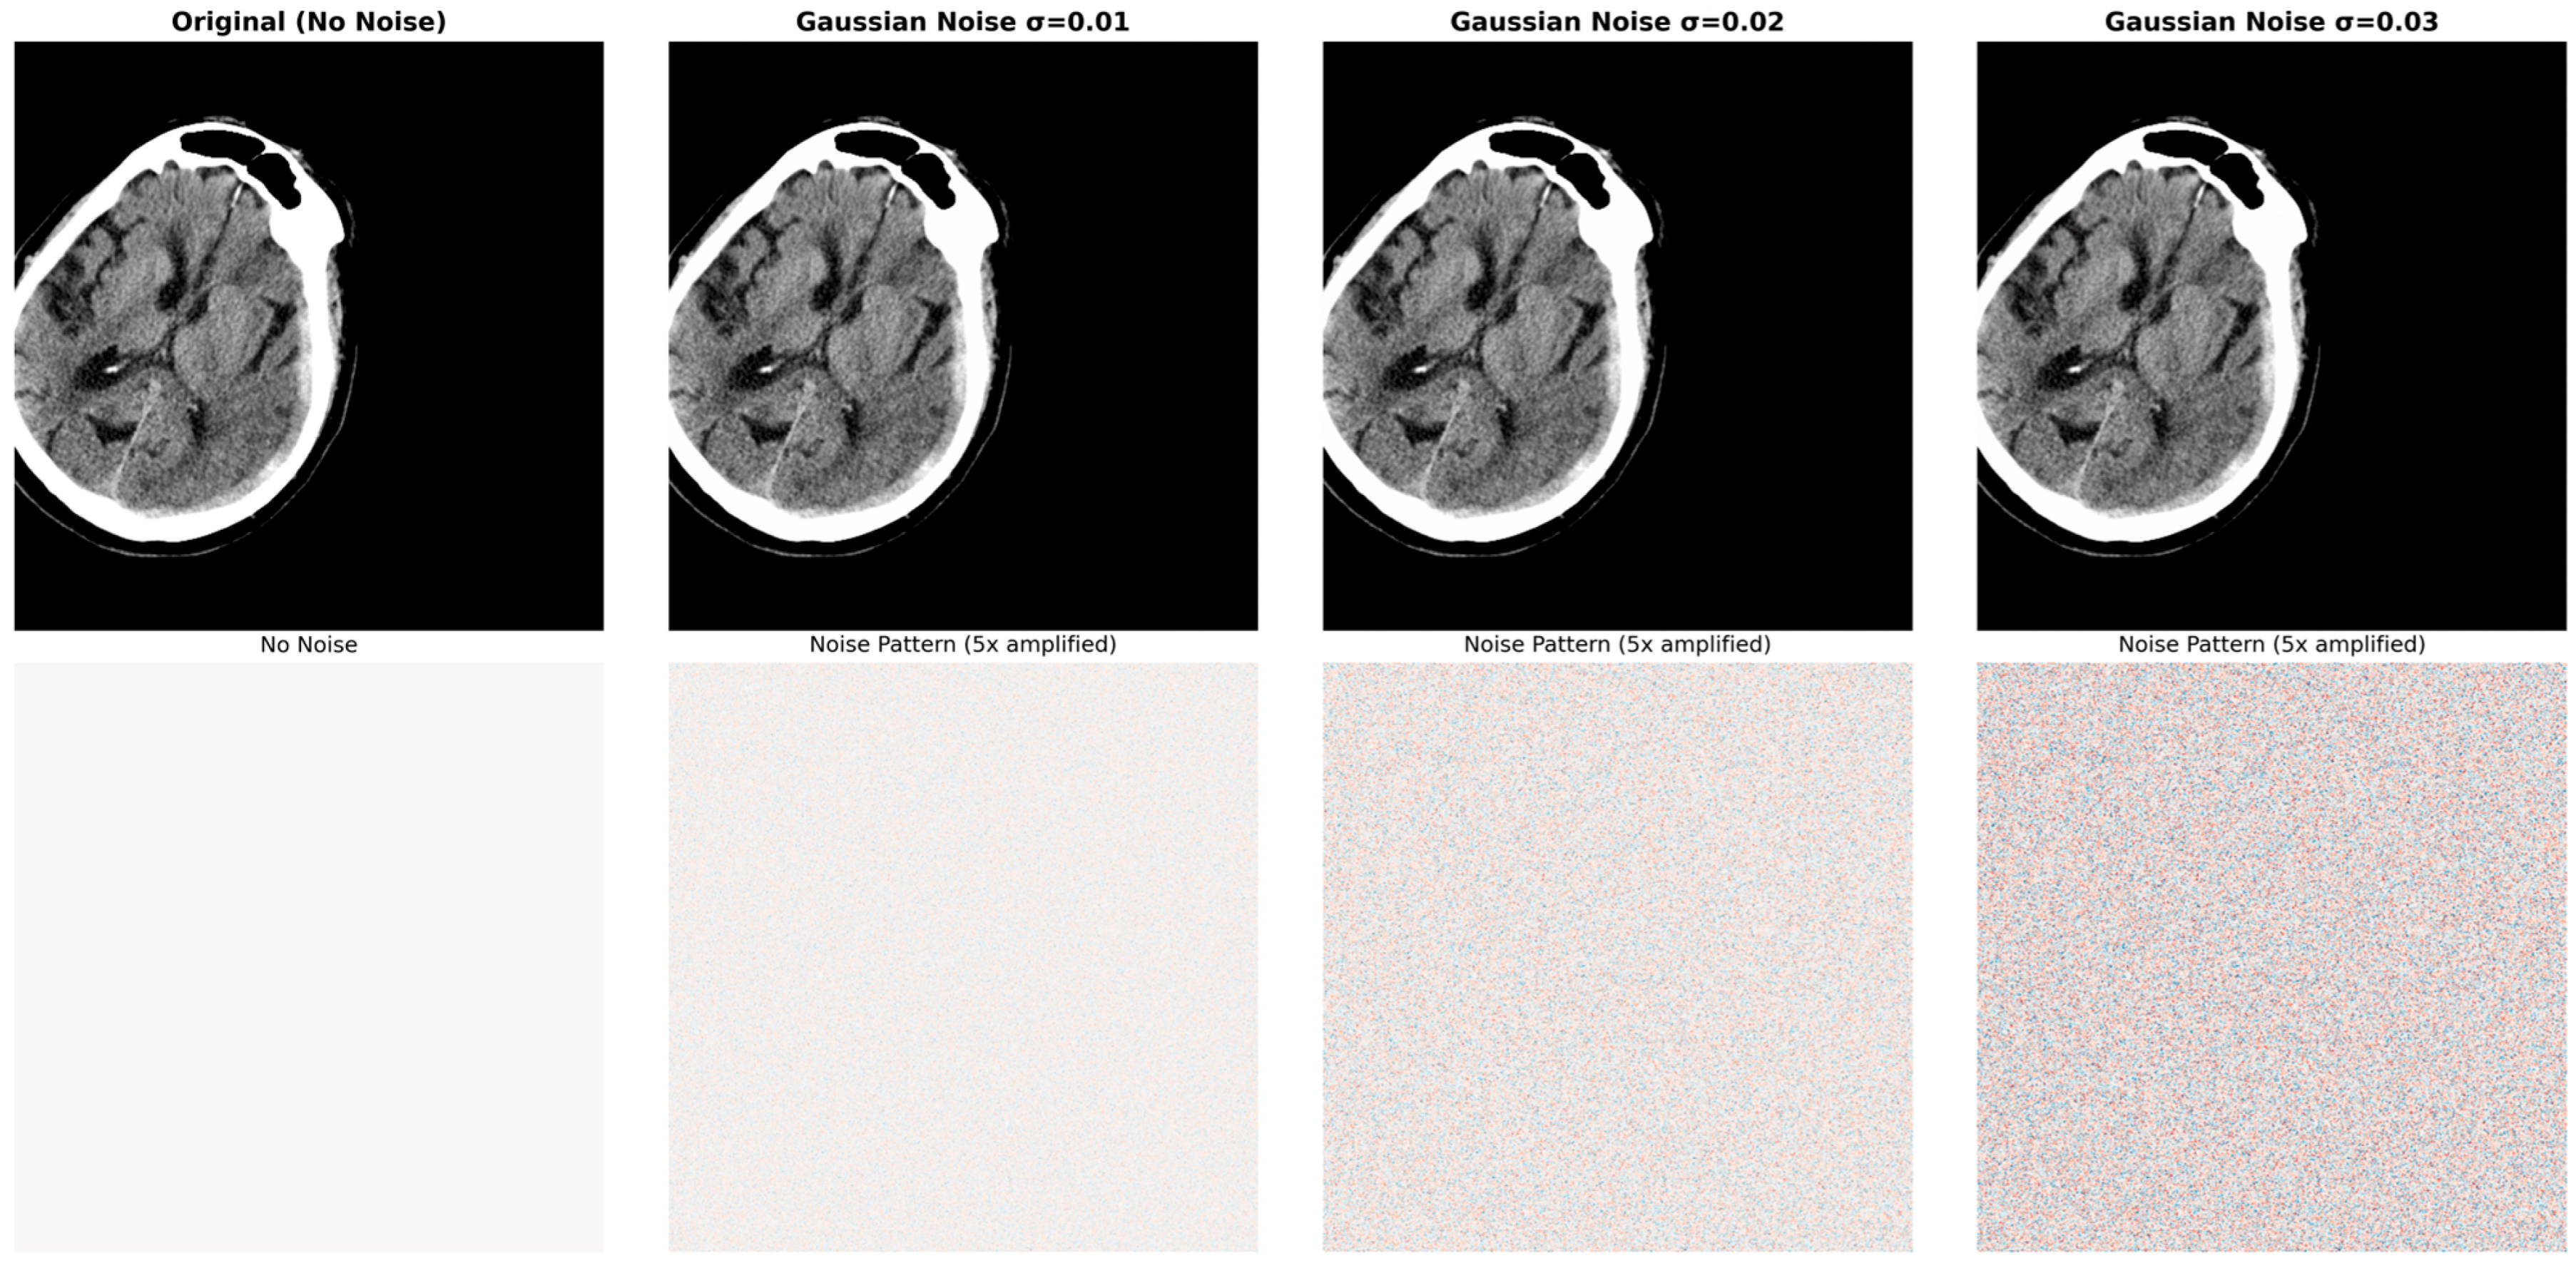

The CLAHE algorithm shown in Figure 8 constitutes the basic component of the contrast enhancement stage. Contrary to the standard histogram equalization method, CLAHE divides the image into small regions (tiles) and applies local histogram equalization in each region. This approach ensures soft tissue differences in CT images become more distinct. As shown in the middle part of the figure, the algorithm consists of three basic steps: dividing the image into 8 × 8 size regions (tiles), applying local histogram equalization in each region, and applying clip limit to prevent excessive contrast increase.

The basic reason for CLAHE being preferred in medical imaging is preventing the excessive contrast increase (over-amplification) that standard histogram equalization can cause. The clip limit parameter (determined as 2.0 in this study) prevents noise amplification by limiting the number of pixels in histogram boxes. This feature is important in terms of preserving fine anatomical details like SP and ventricular structures which are critical in MLS detection.